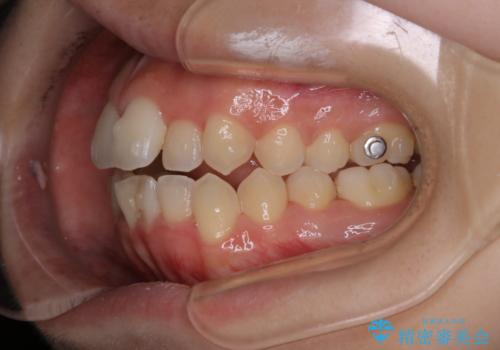

- 矯正装置

- インビザラインFULL

症状としてはオープンバイト(開咬)があり、舌癖も見られました。

日常的に舌を歯に押し付ける癖に対しては舌のトレーニングも併せて行うことで、矯正治療の効率化を図ると同時に後戻りのリスクを最小限に抑えるようにしました。

舌癖がある方は、歯を内側から押し出す力が日常的に働くため、矯正治療後も歯と歯の隙間が開いてしまうなどの後戻りのリスクが高いことが知られています。舌の正しいポジショニングやお口周りの筋肉のトレーニングを行うことで後戻りのリスクを減らすことが可能です。